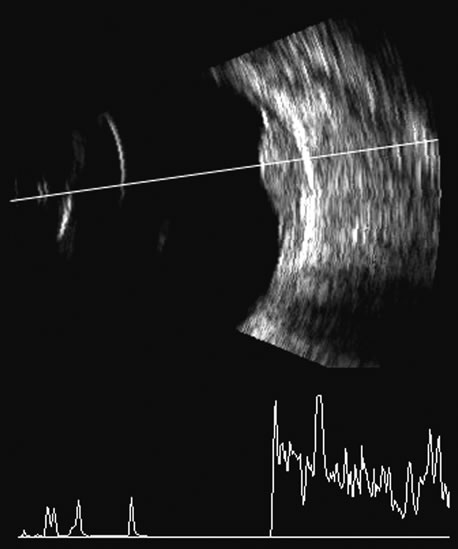

Malignant melanoma varies in its ultrasound presentation from a relatively homogeneous to heterogenous lesion on B-scan. The typical uveal melanoma absorbs sound so that the posterior section is relatively less echoic than the anterior aspect, producing a gradually decreasing amplitude, often to baseline on the A-scan (Fig. 21).

Fig. 21. An ocular tumor at the posterior pole showing the smooth convex border and solid internal reflectants typical of a melanoma.

Melanomas also have varying amounts of melanin, a highly acoustically reflective pigment. As noted, melanomas characteristically show high reflectivity anteriorly, with decreasing reflectance as the sound traverses the tissue. This produces the decreasing amplitude posteriorly in the tumor seen on A-scan and gray-scale B-scan. This effect often enhances the anterior scleral boundary. The posterior tumor border is thus measured as the first “rising” echo from the tumor decline, and it is most easily seen and accurately identified on B-scan.27